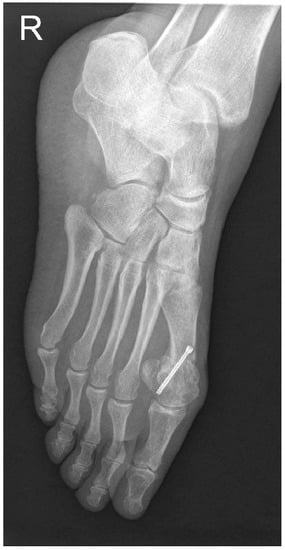

The patients were recruited according to the following inclusion criteria: patients older than 20 years old, failed conservative treatment, and moderate valgus deformity. The hallux valgus severity was preoperatively measured using weight-bearing X-rays, and moderate deformity was defined as a hallux valgus angle (HVA) between 20° and 40° and an intermetatarsal angle (IMA) between 11° and 16° (Figure 1) [36]. The HVA was measured between the axis of the first metatarsal and the longitudinal axis of the proximal phalanx of the first ray [37]. The IMA is formed by the longitudinal axes of the first and second metatarsals. The exclusion criteria applied were patients with previous first metatarsal osteotomy, instability of the first metatarsocuneiform, osteoarthritis of the metatarsophalangeal joint, and systemic diseases that may affect the musculoskeletal system (gout, rheumatoid arthritis, systemic lupus erythematosus, etc.).

We also radiologically evaluated each patient using standard weight-bearing anteroposterior and lateral images of the foot (Figure 1 and Figure 2). The HVA and IMA angles were preoperatively measured using Cedara I-View 6.3.3. At 6 weeks, 6 months, and 12 months, we performed additional radiological images to evaluate the angle modifications.

Figure 1. Preoperative weight-bearing anteroposterior image and measurements of HVA and IMA.